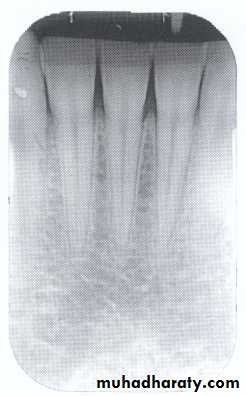

Amount of bone loss

Normal alveolar bone level is 1 - 1.5mm from CEJ.

CEJ

Crest of the remaining crest

Y

The amount of bone loss = Y – 1 mm

Bone loss